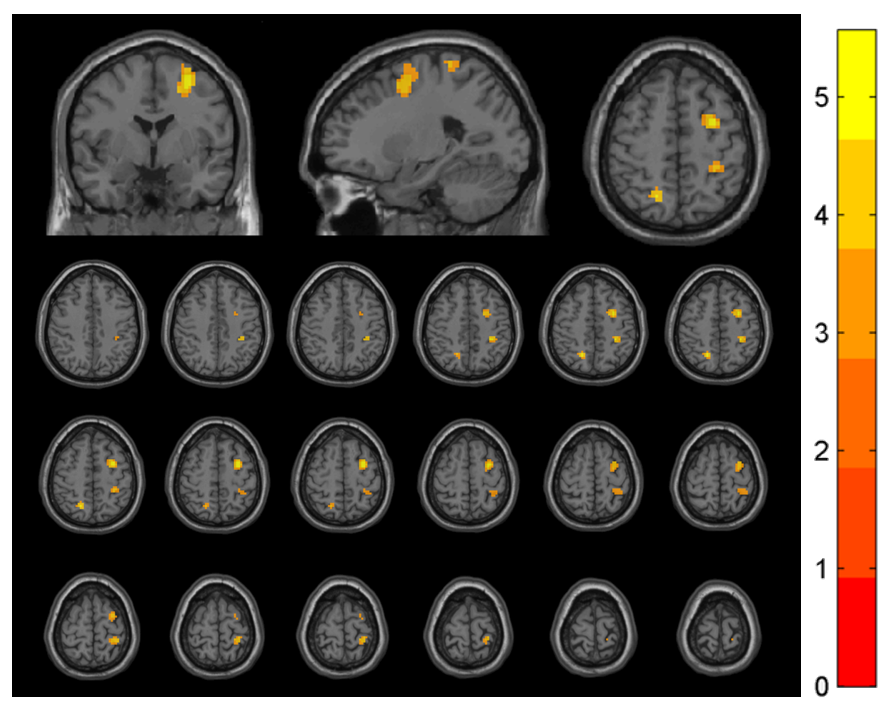

Results: There was no statistical difference in basic data and disease characteristics among three groups (P>0.05). Analysis showed there were significant differences in middle frontal gyrus (MFG), superior frontal gyrus (SFG), postcentral gyrus, precentral gyrus, and superior parietal gyrus (GRF correction, voxel P<0.001, cluster P<0.05)[figure1]. In patients with chronic pain, Reho in above regions were significantly higher (P<0.05 or P<0.001) than those with no pain. In MFG/SFG (P<0.01), postcentral/precentral gyrus (P<0.001), Reho in patients with chronic pain were significantly higher than HC, but in superior parietal gyrus were lower (P<0.05) than HC. In patients with no pain, they had decreased Reho in superior parietal gyrus (P<0.001) compared with HC.

ReHo Differences in Brain Regions Across Groups